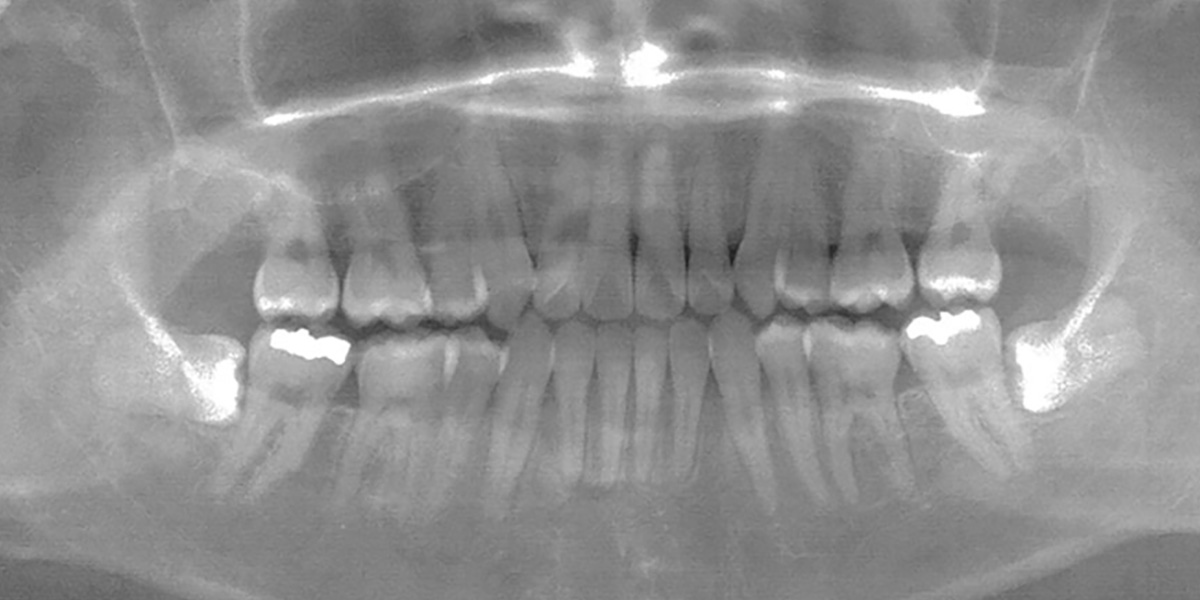

■ レントゲン(治療前)